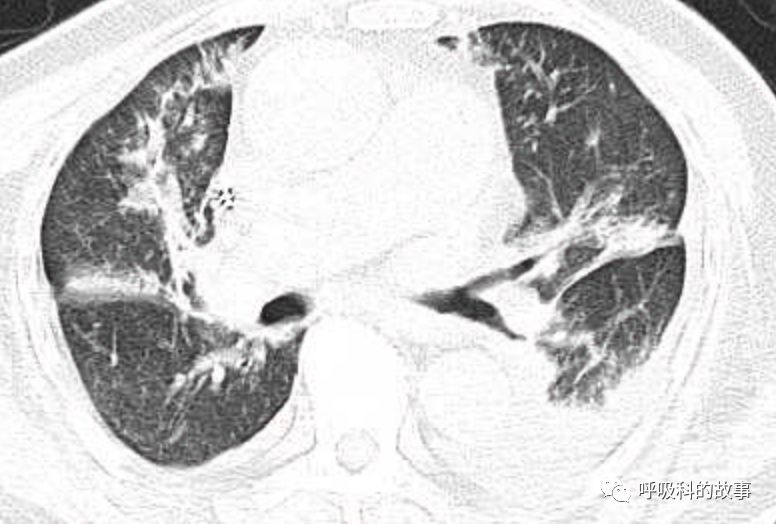

肺部CT如下:

以上的CT给我第一眼的感觉是肺炎,再结合患者有发热和血炎症指标明显增高,肺炎的诊断应该没有问题,但是胸水又是漏出液,结合脑钠肽增高和患者有胸闷气急的症状,心功能不全的诊断也能成立。在某些层面,肺部实变影以内中带为主,还要考虑肺水肿的诊断。入院后给予患者美罗培南抗感染、托拉塞米利尿治疗,以及化痰、雾化处理,患者体温在入院后三天就正常了,入院第五天复查NT-proBNP3390pg/ml;血常规示白细胞 13.5*10^9/L,中性粒细胞81.8%,淋巴细胞13.2%,超敏C-反应蛋白 25mg/L;电解质示钠 160mmol/L,氯 111mmol/L 。虽然炎症指标和心功能指标均有好转,但患者却仍旧精神差,每次查房时仍然表现嗜睡状,家属也反映患者不论白天还是夜晚多数时间不是太清醒。那么问题出在哪里呢?